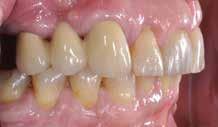

Der planlægges alignerbehandling af begge kæber med intrusion af 1+1 og 2,1-1,2, nivellering af trangstilling UK med interproksimal reduktion (IPR) (Fig. 2 A, B) og senere IPR OK for reduktion af dark triangles mellem incisiverne efter nivellering. Patienten instrueres i at benytte alignere 20-22 timer/ dag med alignerskift hver 7. dag, og patienten ses hver 3.-8. uge under forløbet. Den første alignerserie består af 16 alignere for nivellering OK/UK og IPR i UK (Fig. 2). Efter denne serie planlægges IPR mellem incisiverne i OK for reduktion af dark triangles (Fig. 3) samt yderligere intrusion af OK og UK-fronten i 12 refinement-alignere. Patienten udviser god kooperation og er meget tilfreds med alignerapparaturet, som er mindre synligt end det faste apparatur (Fig. 4).

Behandlingen afsluttes med yderligere refinement-alignere for finindstilling af okklusionen, og efter 11 måneders ortodontisk behandling er der opnået normale relationer i alle tre